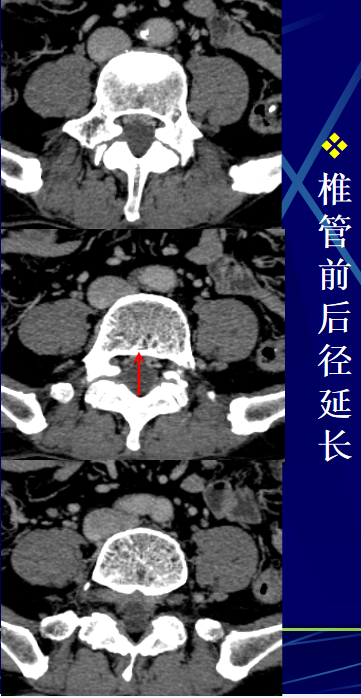

• 腰椎后缘软骨结节是椎间盘组织经终板疝入椎体后上部或后下部松质骨内,使腰椎后缘小骨块突入椎管,致椎管狭窄及压迫脊神经根的一种疾病。

• 病理证实除骨块外均系透明软骨和退变的椎间盘组织。

• CT诊断依据::位于椎体上、下的后缘,病灶呈类圆形或多环形的骨缺损,密度与椎间盘相似,周边有反应性骨质硬化,结节的骨性后壁呈弧形凸入椎管,后壁与椎体相连或不连。骨块后缘与突出的腰椎间盘后缘在CT扫描下显示一致,说明骨块是伴随椎间盘同时向椎管内突出的。

椎体后缘软骨结节的发生机理:椎体后缘软骨结节多发生于青少年,  一般认为是青少年时期在解剖缺陷的基础上,在各种应力(主要是纵向挤压)的作用下,特别是伴有屈曲旋转时,髓核的膨胀压力使间盘组织穿过软骨板突入到椎体与骨突环之间的薄弱区,并逐渐扩大形成软骨结节。相邻骨突环受压后移,并继续骨化,形成软骨结节的骨性后壁。部分软骨结节的骨性后壁断裂不连续,少数软骨结节由此突入椎管。

椎体后缘软骨结节多发生于腰骶椎(其中以L5最多,其次S1,再次是由L5向上的各个腰椎,由下向上发病率依次减),极少数发生于不参与胸廓构成的T11、12。颈椎未见发病报告。

根据部位可分为以下几型:(1)上缘正中型:最多见,约占47%,易压迫硬膜囊,较大时可压迫硬膜囊和神经根。

(2)上缘偏侧型:约占25%,易压迫硬膜囊和同侧神经根。

(3)下缘正中型:约占25%,压迫硬膜囊。

(4)下缘偏侧型:很少见,约占3%,压迫硬膜囊及同侧神经根。